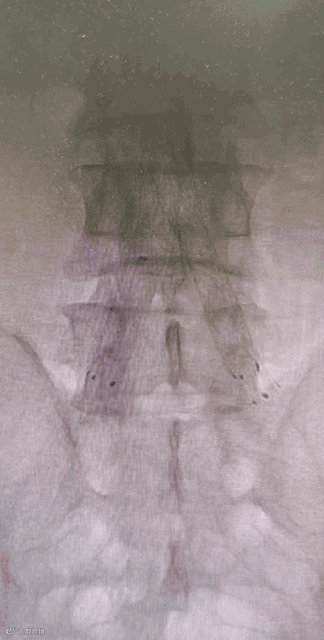

Separator With Aspiration catheter for Mechanical Thrombectomy(MT)【分离器辅助导管抽吸技术】:旨在提高整体系统的抽吸效率和治疗安全性,快速帮助血栓清除。

1)抽吸导管头端堵管,分离器可以快速疏通导管,降低撤管冲洗的频率。

2)针对大负荷血栓或亚急性血栓,分离器辅助下抽吸能提升整体系统抽吸效率,缩短手术时间。